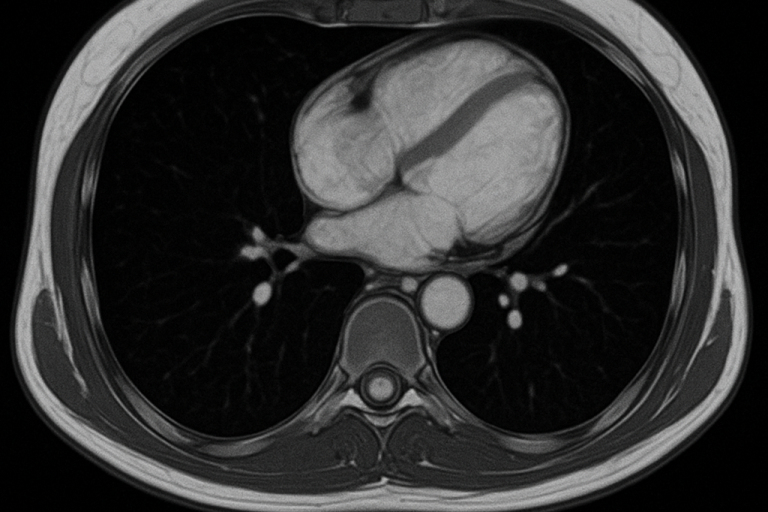

Herz-MRT

Das Herz-MRT (Kardio-MRT) ist ein modernes, strahlenfreies Verfahren zur detaillierten Beurteilung von Herzstruktur und Herzfunktion. Mithilfe starker Magnetfelder und Radiowellen lassen sich die Herzkammern, Herzklappen und der Herzmuskel präzise darstellen. Die Untersuchung ermöglicht die Erkennung von Durchblutungsstörungen, Herzmuskelerkrankungen (Kardiomyopathien), Entzündungen oder Narben nach einem Herzinfarkt. Auch die Pumpfunktion und die Gewebebeschaffenheit des Herzens können genau analysiert werden. Das Herz-MRT dient sowohl der Diagnose als auch der Verlaufskontrolle vieler Herzerkrankungen und unterstützt eine gezielte Therapieplanung.